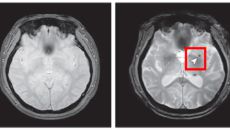

단순한 코골이 아닙니다…심한 수면무호흡증, 뇌 미세출혈 위험 2배 높여

심한 수면무호흡증이 있는 사람은 없는 사람에 비해 뇌 미세출혈이 발생할 위험이 2배 넘게 높다는 연구 결과가 나왔다. 수면무호- 2025.12.03 15:29